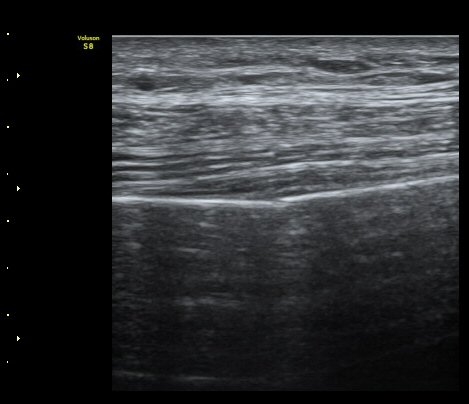

ÃÊÀ½ÆÄ °Ë»ç

¹Ì¼¼ÇÏ°Ô °¥ºñ»À ÇÇÁú°ñ ¿¬°á¼º ¼Ò½Ç°ú ¿¬ºÎÁ¶Á÷ ºÎÁ¾ÀÌ °üÂûµÊ (loss of cortical continuity and soft tissue swelling of rib) »çÁø 1